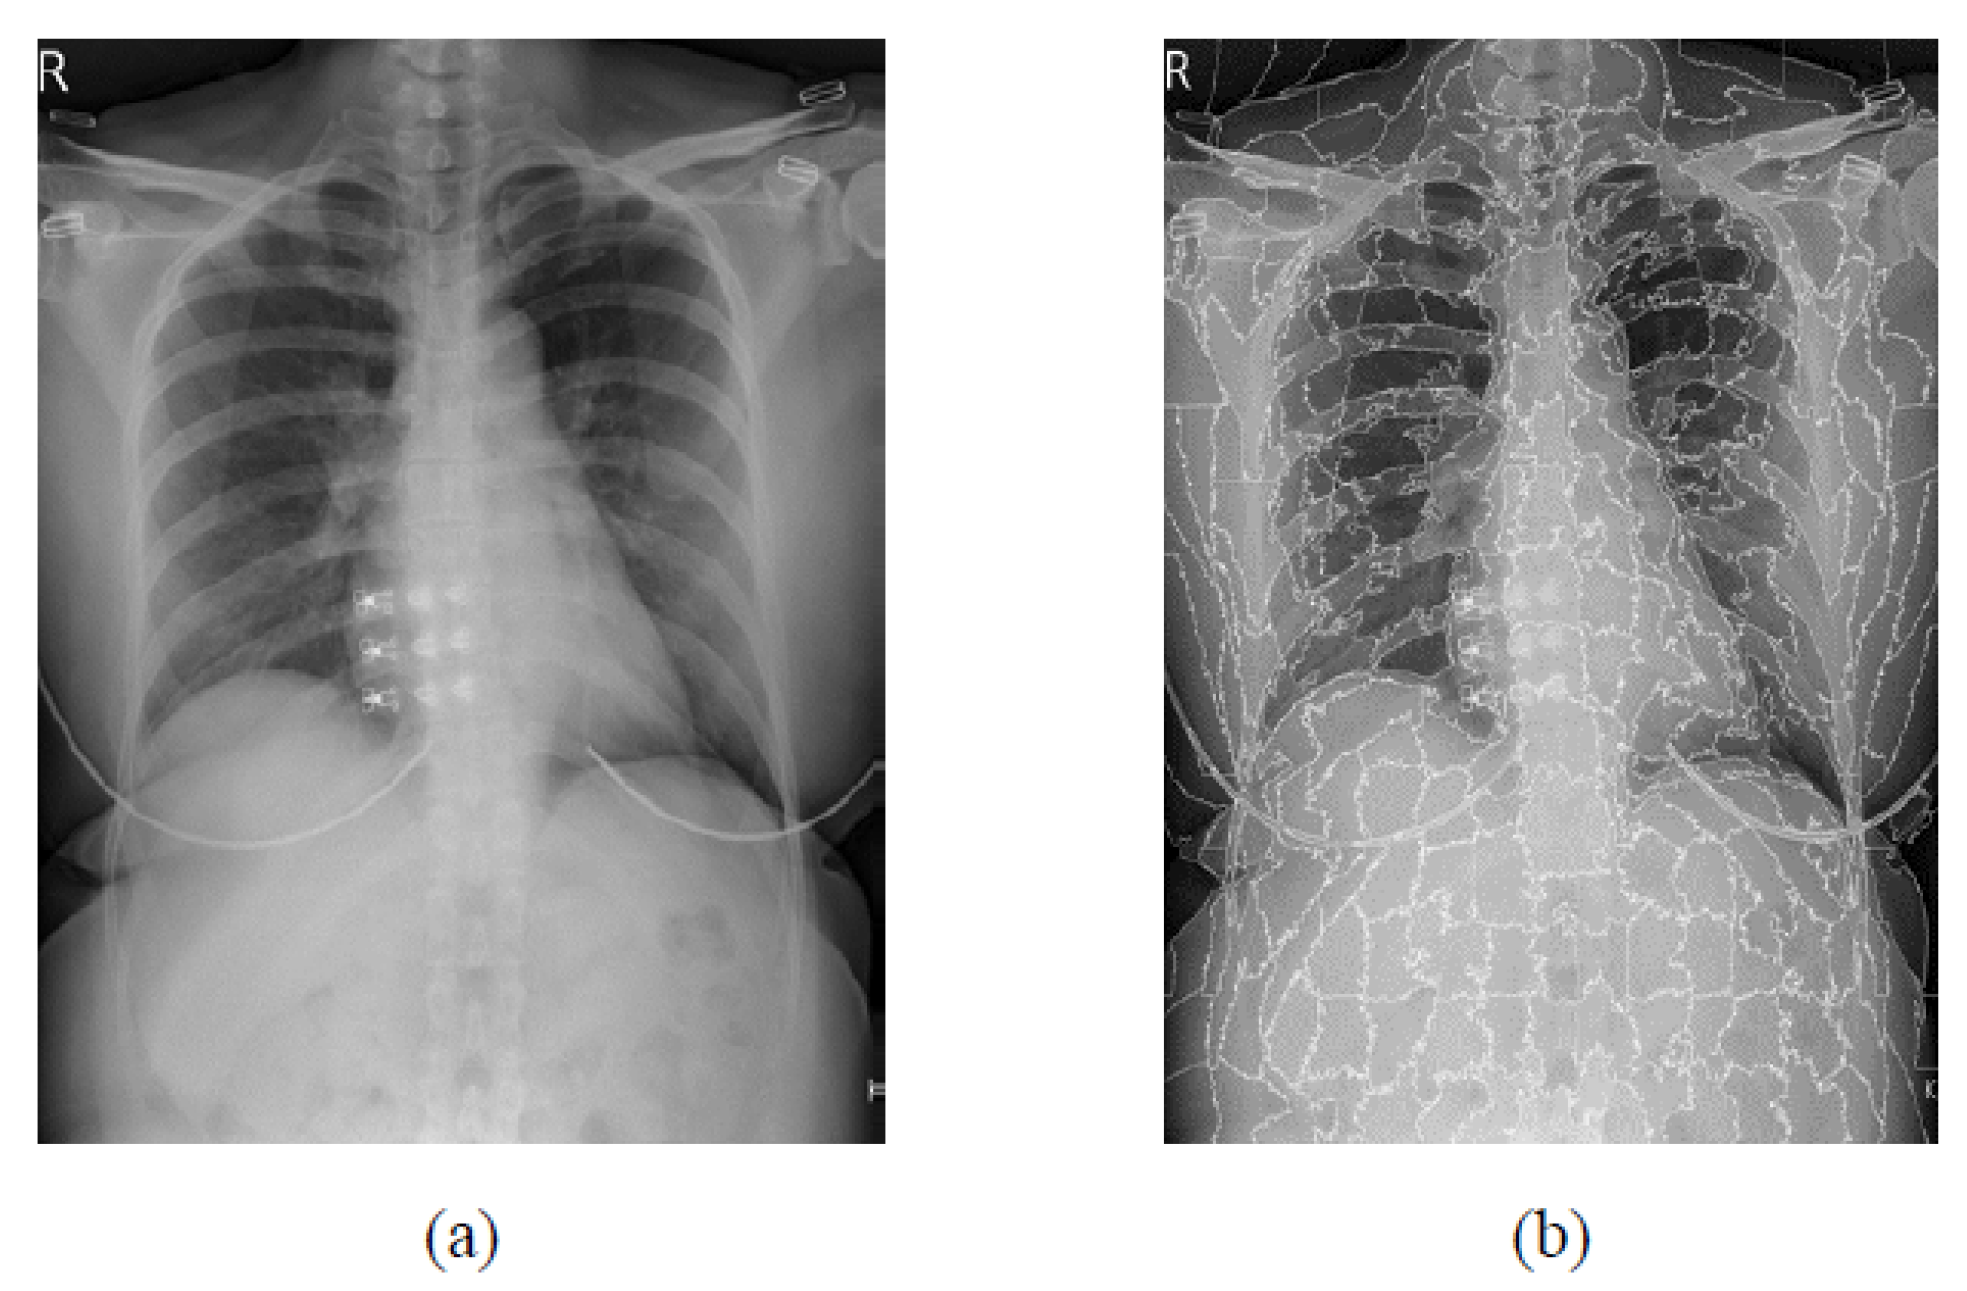

3.3. USEQ Superpixel Extraction

3.4. USEQ Superpixel Resizing Framework